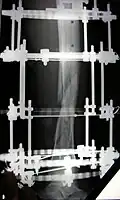

The photographs and radiographs illustrate the application and emplacement of an external fixator, an Ilizarov apparatus, to repair the open fracture of the lower left leg of a man. The photographs were taken four weeks after the patient fractured the shinbone (tibia) and the calfbone (fibula) of his left leg, and two weeks after the surgical emplacement of the Ilizarov apparatus to immobilise the leg and isolate the wound and fracture site to facilitate healing.

X-ray of the fracture site and the emplaced apparatus, two months post-fracture; perspective 1-4. -

X-ray of the fracture site and the emplaced apparatus, two months post-fracture; perspective 2-4. -